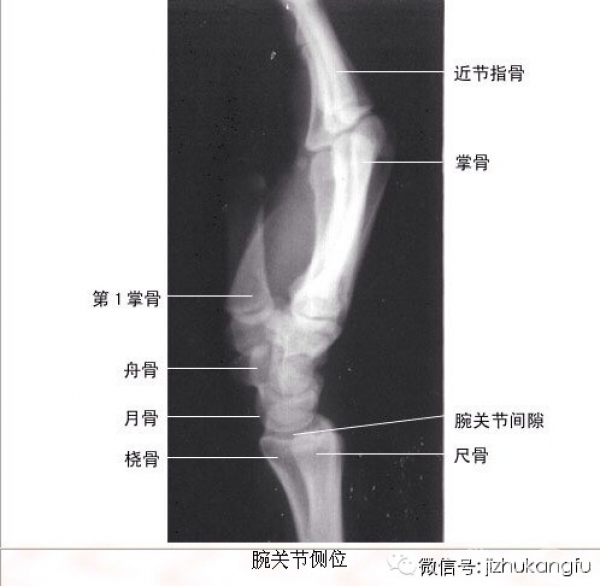

1四肢关节